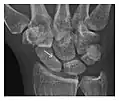

Occult osseous injuries may result from a direct blow to the bone by compressive forces of adjacent bones against one another or by traction forces during an avulsion injury. Lesions in the tibial plateau, hip, ankle, and wrist are often missed. In a tibial plateau fracture, any disruption of the posterior and anterior cortical rims of the plateau should be sought. Impaction of subchondral bone will appear as an increased sclerosis of the subchondral bone (Figure 1). In the hip, posterior acetabular fractures also present subtle radiographic findings. The acetabular lines should then be carefully examined keeping in mind that the posterior rim, which is harder to see on X-rays, is more frequently fractured than the anterior rim (Figure 2). In the wrist, detection of carpal bone fractures is often challenging, with up to 18% of scaphoid fractures radiographically occult. Carpal fractures, especially the scaphoid, are associated with the risk of avascular necrosis. In apparently normal wrist radiographs from symptomatic patients, if there is history of a fall on an outstretched hand with pain in the anatomic snuffbox, suggesting scaphoid injury, the initial examination with posteroanterior, lateral, and pronation oblique views must be complemented by other specific views such as supination oblique and the "scaphoid" view A careful examination of cortices for evidence of discontinuity or offset and cancellous bone for lucency is necessary (Figure 3).[1]

-

a

b

c

Figure 3: A 26-year-old man presenting with wrist pain after being assaulted. (a) Initial anteroposterior radiograph shows a subtle linear lucency within the scaphoid extending to the scaphocapitate articular surface that was overlooked (arrow). (b) Initial "scaphoid" view was negative. (c) Followup anteroposterior radiographs, 12 days later, shows obvious scaphoid fracture (arrows).[1]